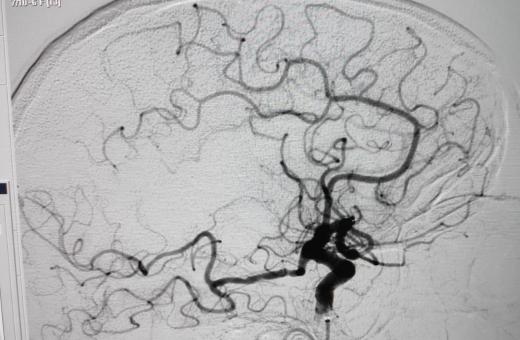

28/10/2020 El Trueta arriba a les cent primeres trombectomies en pacients que han patit un ictus isquèmic agut